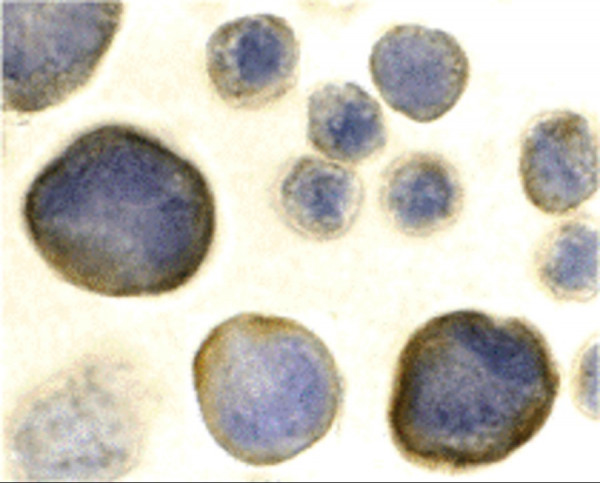

| Application: | ELISA, FC, ICC, IF, IHC (paraffin), IHC (frozen), IP, WB |